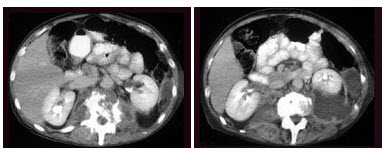

男,56岁,无痛性全程血尿1月,CT平扫及增强检查如图,下列说法正确的是()

A.右肾上极,肾脏局部隆起,平扫时其密度与肾相近,不易分辨其轮廓

B.增强扫描皮质期,病灶强化明显,但仍低于肾皮质的强化

C.增强扫描实质期,病灶强化迅速减退,可清楚的分辨其轮廓

D.右肾静脉及下腔静脉内未见充盈缺损影

E.考虑为右肾上极的肾癌